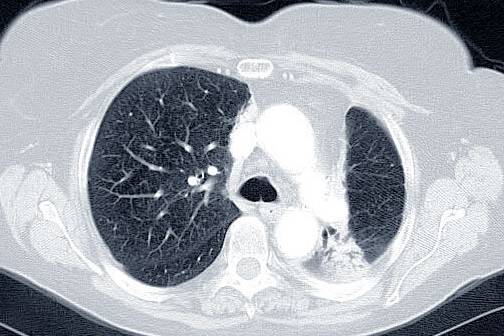

真假支气管爬行征肺腺癌1例ct影像讨论

5个经典病例读懂肺癌诊断

肺癌ct

肺癌ct图片